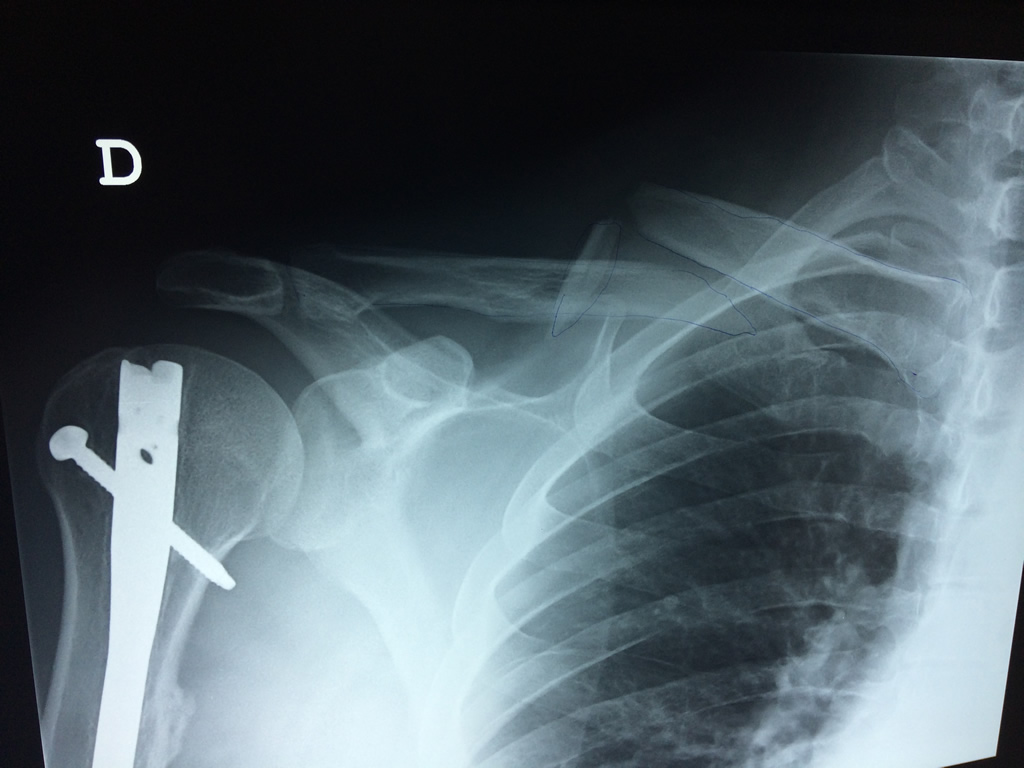

Cirugias en El Salvador - Clavícula